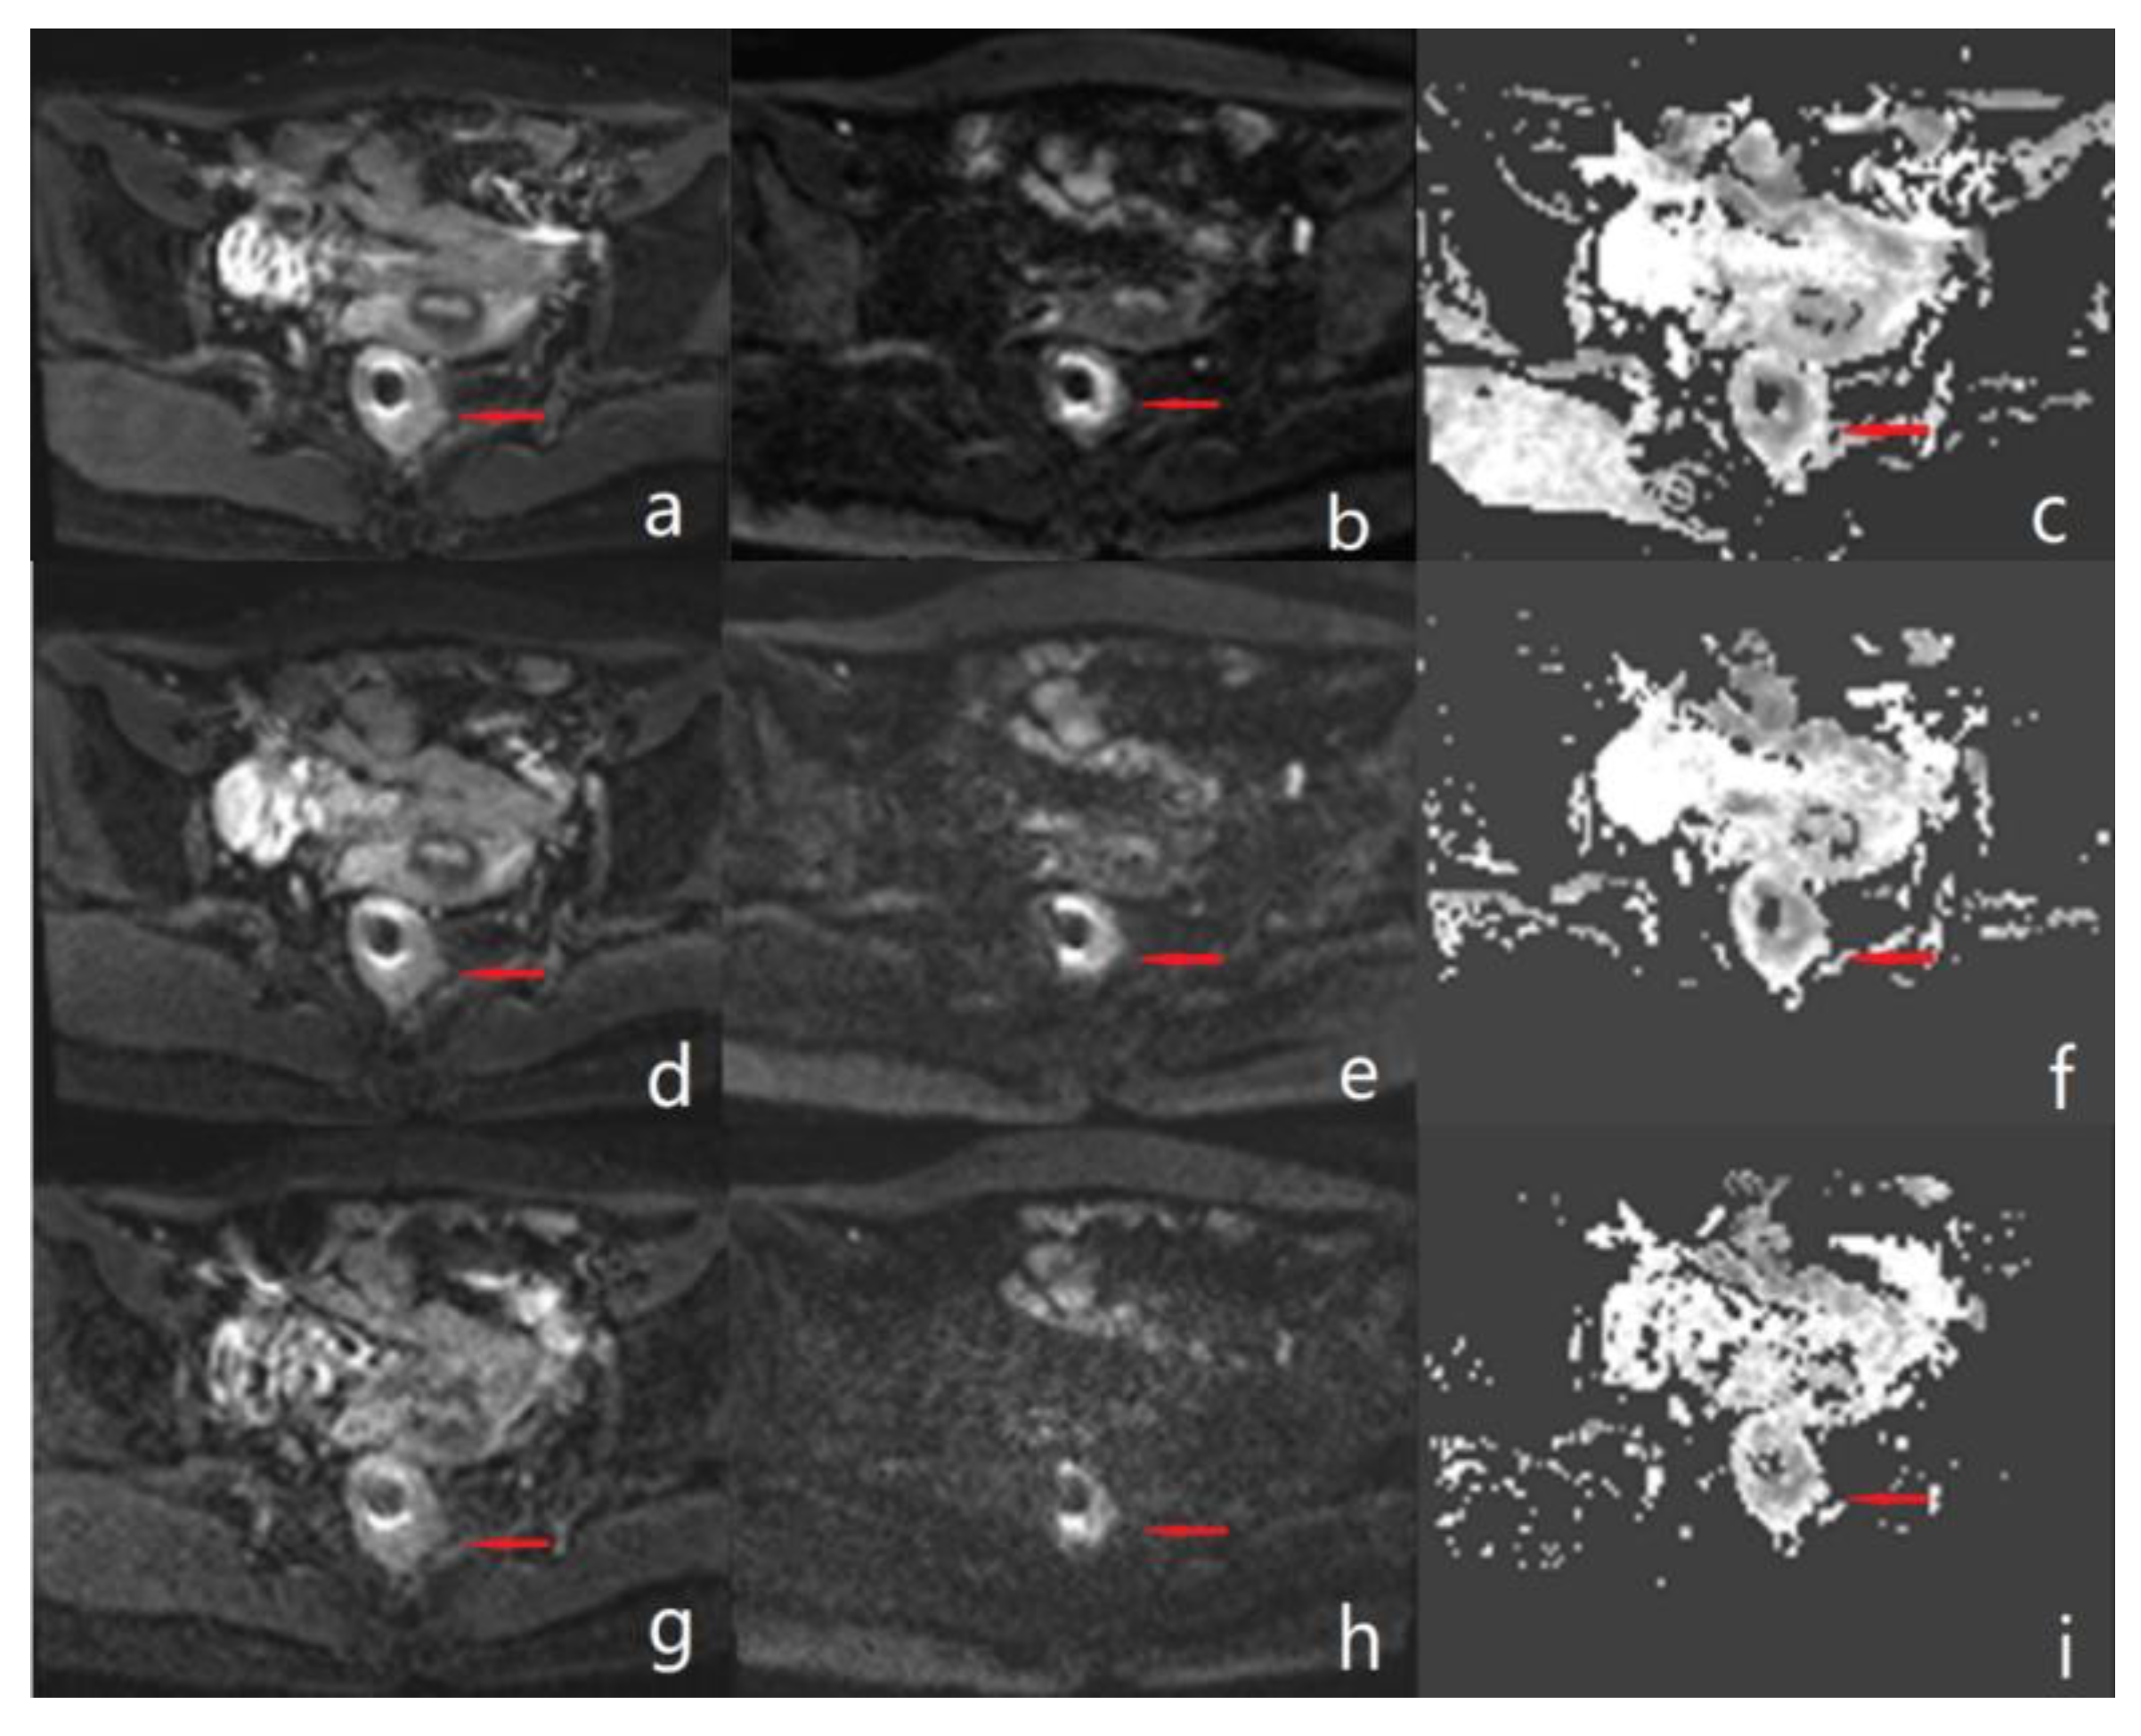

Figure 3.

Male, 53 years old with rectal cancer. (a–c) Diffusion-weighted and ADC maps of conventional rs-EPI sequences with b-values of 0 s/mm2 and 1000 s/mm2, respectively. (d–f) Diffusion-weighted and ADC maps of 2 × SMS rs-EPI sequences with b-values of 0 s/mm2 and 1000 s/mm2, respectively. (g–i) Diffusion-weighted and ADC maps of 3 × SMS rs-EPI sequences with b-values of 0 s/mm2 and 1000 s/mm2, respectively. The arrow in the figure points to a rectal cancer lesion.

The scores of lesion conspicuity, overall image quality and margin sharpness on DWI images and ADC map were significantly different among rs-EPI, 2 × SMS rs-EPI, and 3 × SMS rs-EPI (p < 0.05), while there were no significant different between 2 × SMS rs-EPI and rs-EPI (all p > 0.05). In the b = 1000 s/mm2 DWI image of the 3 × SMS rs-EPI sequence, parallel acquisition artifacts can be seen, and rectal structures were poorly visualized (Table 3 and Figure 2andFigure 3).

Our study found that, using an AF of 2, 2 × SMS rs-EPI allowed for a considerable reduction of acquisition time while maintaining high diagnostic image quality and lesion conspicuity. When increasing the AF to 3, a significant deterioration in image quality was observed in patients with reduced visibility of all organ parts in the diffusion weighted images and reduced image quality of the corresponding ADC maps. Moreover, artefacts and signal inhomogeneity in 3 × SMS rs-EPI were significantly increased, which led to a poorer overall image quality and to a limited lesion conspicuity, thus discarding the use of higher AFs for clinical routine applications in its current implementation. Based on these results, further evaluation of AFs higher than 3 was waived.